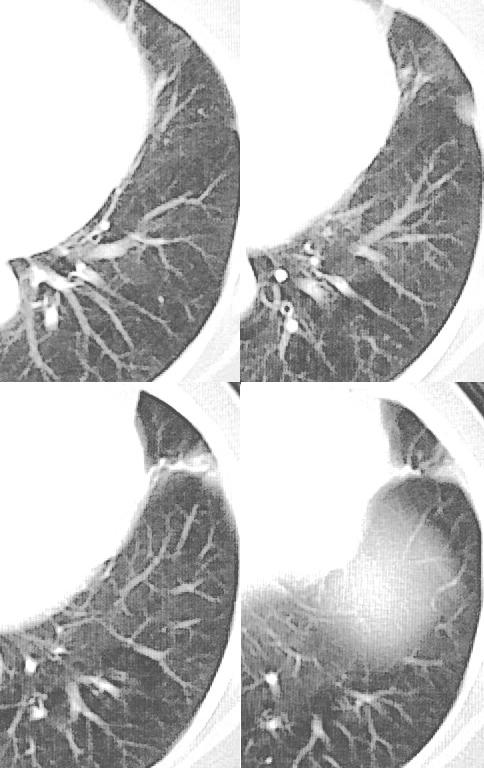

女,52岁,咳嗽,咳痰多日

考虑慢性炎性病灶粘连牵拉改变。

左肺舌叶纤维锁条病变。

左肺上叶下舌段炎症并局部胸膜反应。

左肺舌叶纤维索条影。

左肺舌叶段陈旧性病变

左肺舌叶纤维索条影